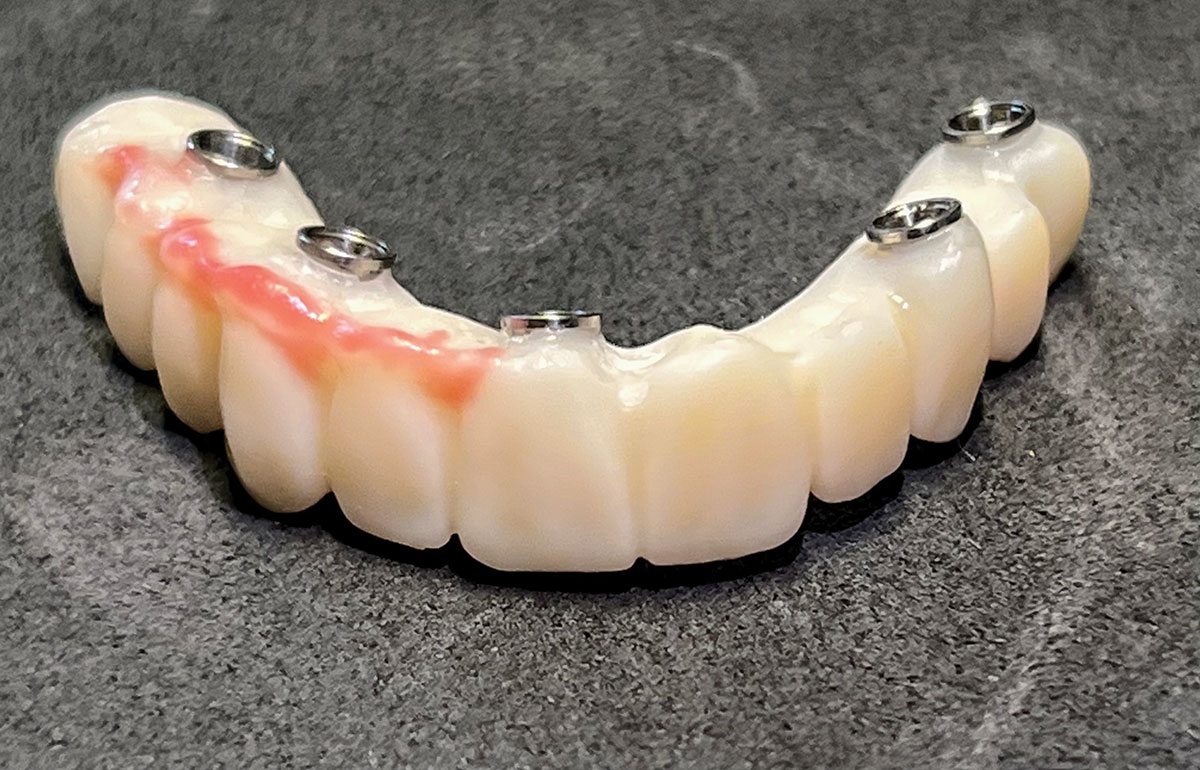

At the next visit, the patient was anesthetized with xylocaine with 1:100,000 epinephrine. Teeth Nos. 22, 27, and 28 were retained and all other mandibular teeth were extracted. Immediate implants were placed in prosthetically correct positions and multi-unit abutments were torqued to 30 Ncm. This was followed by insertion of screw-retained scan gauges in positions Nos. 18, 24, and 30.

This file was then electronically returned to the dental team via the proprietary web portal. The office staff then sent the STL design file to the practice's 3D printer software, and the appropriate color nanoceramic resin was used to print the prosthesis at 100 microns. Once this was accomplished, the prosthesis was stained and glazed and gingival color was applied to establish optimum esthetics.

The completed prosthesis was then screwed directly onto the multi-unit abutments with Rosen screws with no ti-bases and torqued to 20 Ncm. Screw-access holes were filled, and no occlusal adjustment was necessary. The fit of the prosthesis was precise and stable and the phonetics of the patient was ideal. The patient was overwhelmed by the significant esthetic improvement with this set of teeth in place.

Fig 31. Mandibular provisional prosthesis printed demonstrating screw-access holes in prosthetically correct positions.

Figure 31